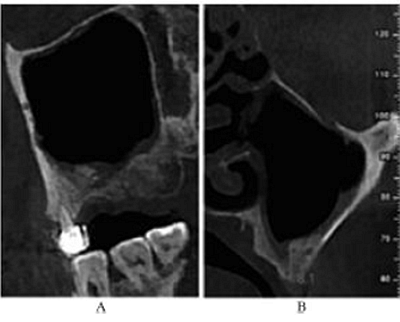

術后5個月,患者無流涕、鼻塞,無其他自覺癥狀。CBCT示:左側鼻甲基本恢復正常,上頜竇高密度影較前明顯減少,仍有少量黏膜增厚。26牙RBH8.1mm,27牙RBH8.4mm(圖4)。擬26~28牙種植修復

圖4 種植前CBCT。注:A,矢狀面;B,26頰舌向切面;C,27頰舌向切面;D,28頰舌向切面。